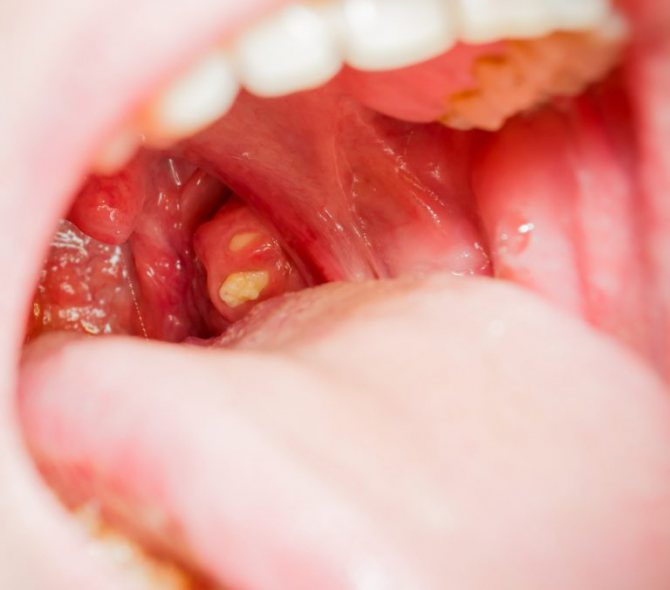

- формированию застоя содержимого лакун и образованию гнойных пробок;

- образованию рубцов, которые полностью закрывают некоторые лакуны, а инфекционное содержимое находится внутри них.

Иммунная система претерпевает значительные изменения, поэтому хронический тонзиллит относят к аутоиммунным заболеваниям. Измененные миндалины перестают выполнять свою функцию и превращаются в хронический источник инфекции. Малейшая инфекционная атака извне вызывает клинически тяжелые ОРВИ, ангины, а постоянное присутствие патологической микрофлоры приводит к развитию резистентности к антибиотикам и противовирусным препаратам, в с каждым разом усложняя лечение ЛОР-заболеваний.

Хронический очаг инфекции, который постоянно находится в миндалинах, является источником токсинов, которые отравляют организм, еще больше угнетают иммунитет. Токсические продукты разносятся с током крови по внутренним органам и поражают их (бактериальное повреждение клапанов сердца, почечной ткани, суставов), но больше всего «достается» близ лежащим структурам, и человека/ребенка постоянно преследуют отиты, риниты и конъюнктивиты.

Гипертрофированная измененная лимфоидная ткань нарушает дыхание, нормальный сон и даже речь. Поэтому проблема тонзилэктомии часто всего возникает в детском возрасте, порою имея и жизненные показания.